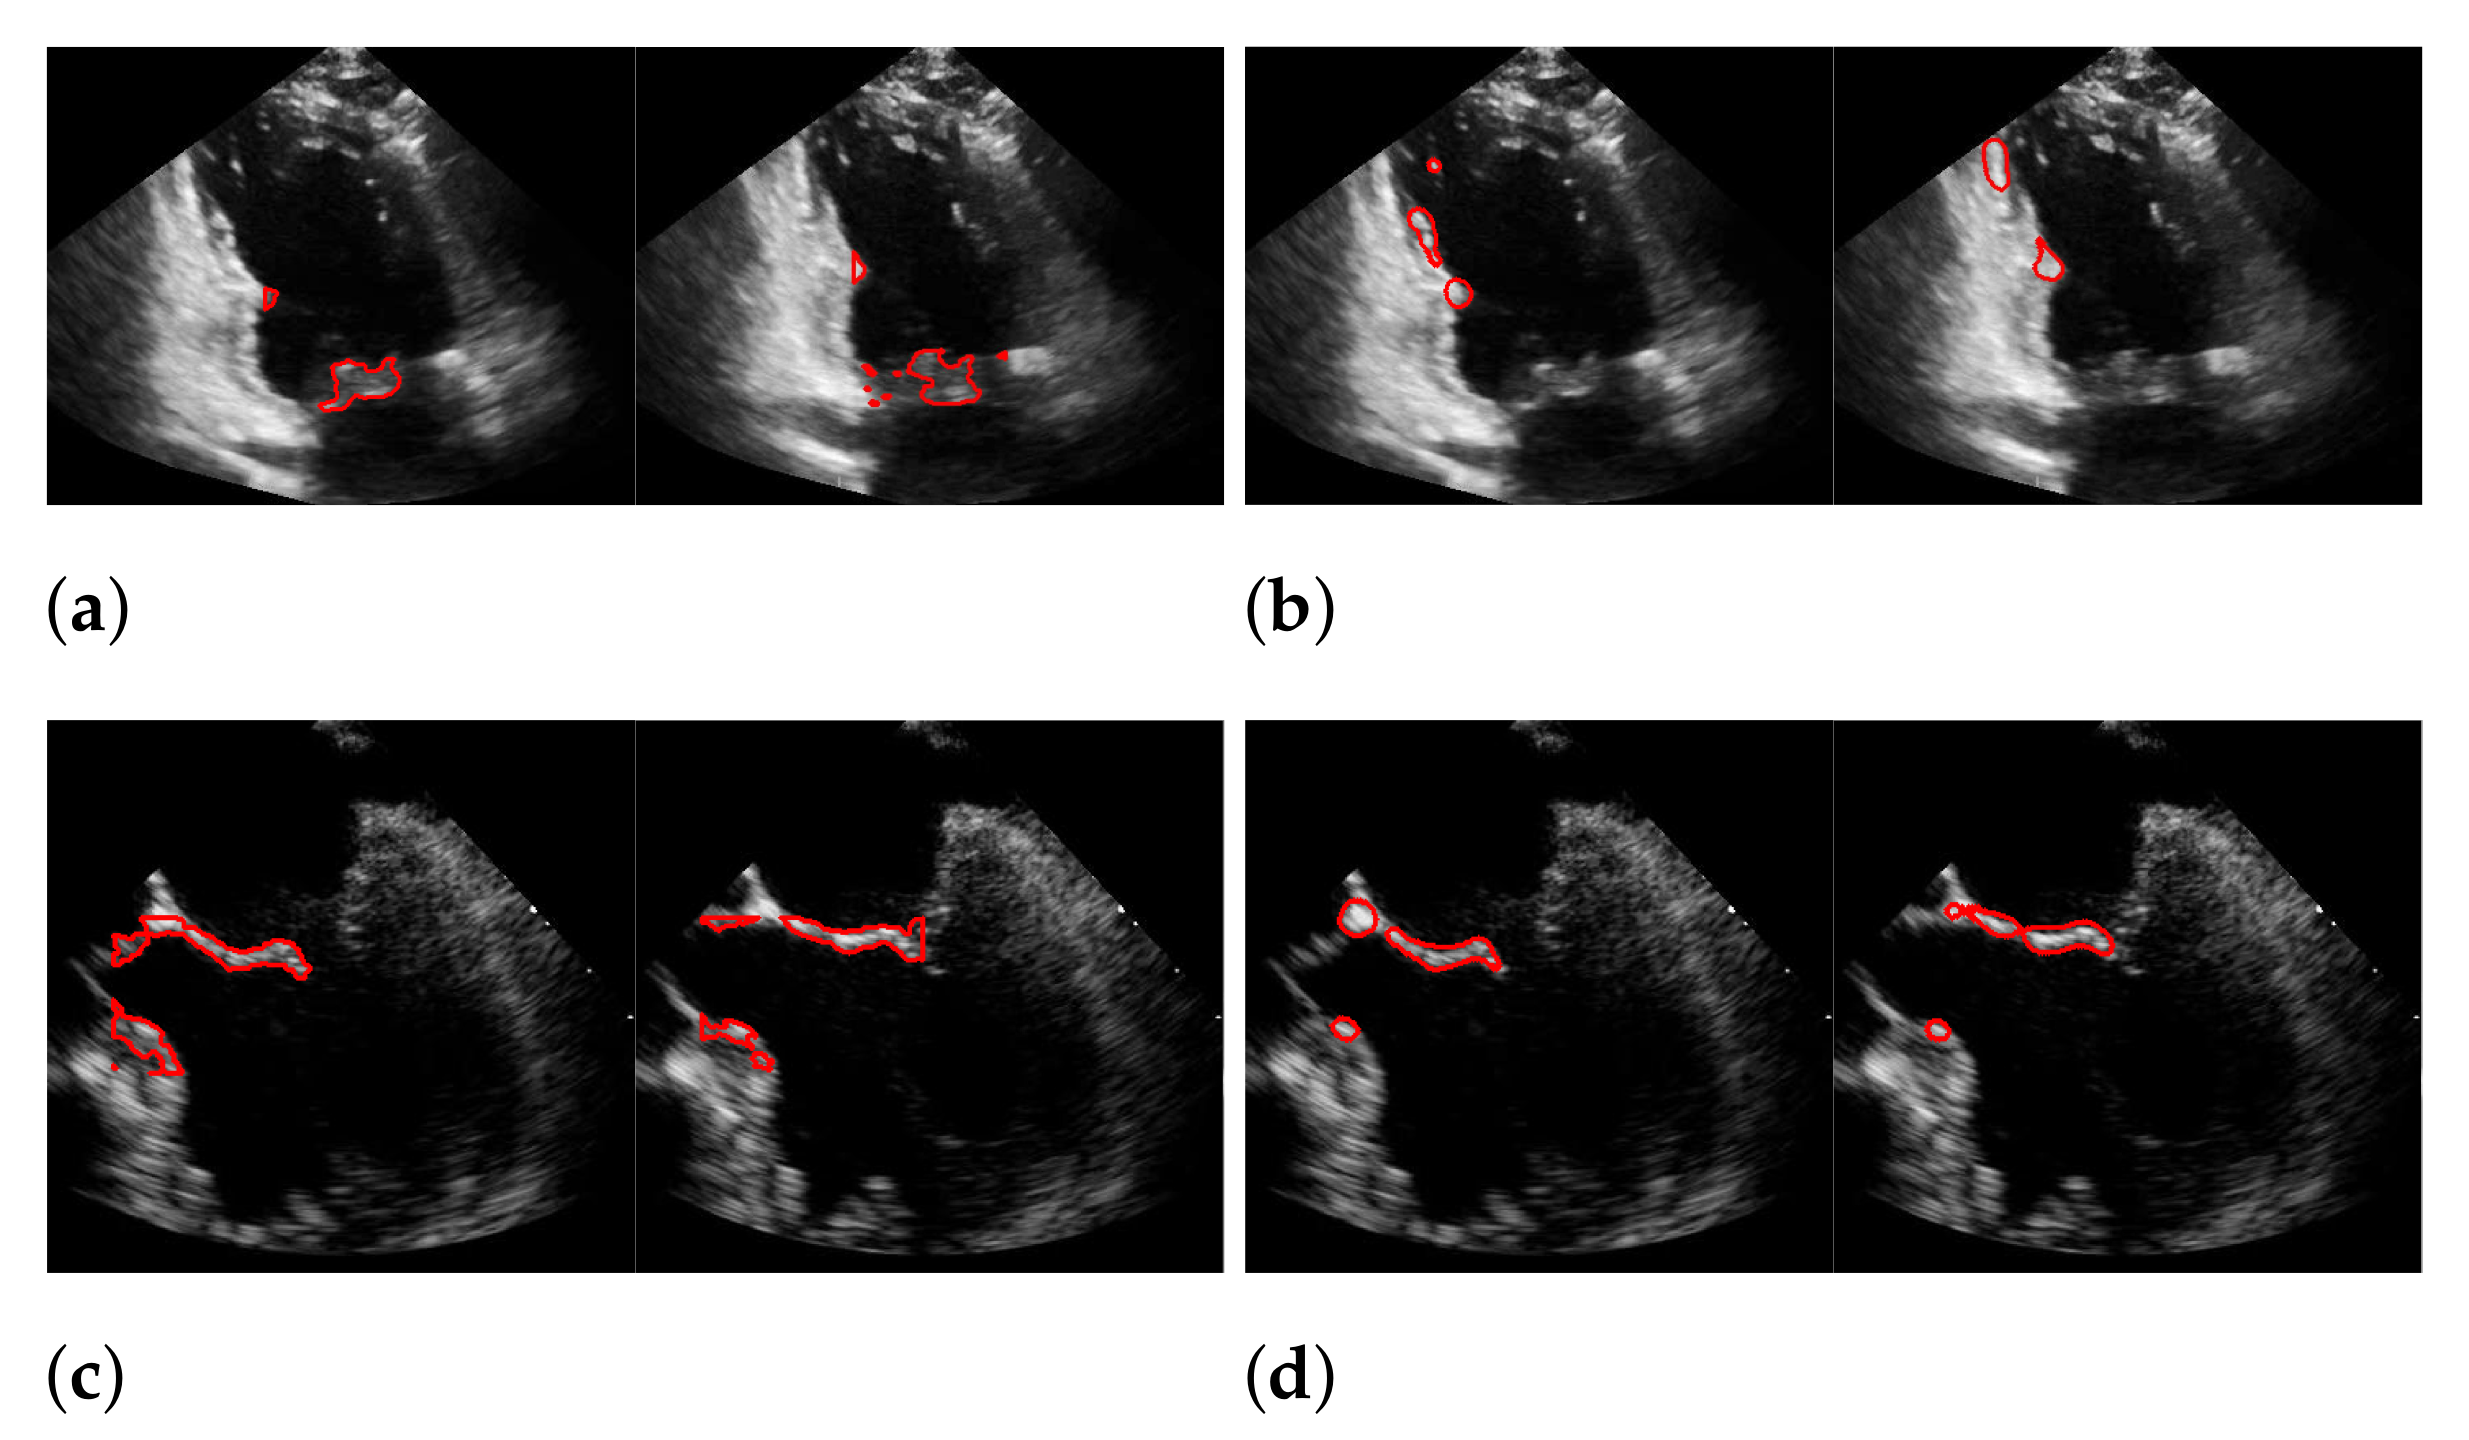

5.2. Automatic Segmentation

| Recall | Precision | f1-Score | |

|---|---|---|---|

| (a) | 0.494 | 0.692 | 0.565 |

| (b) | 0.44 | 0.558 | 0.45 |

| (c) | 0.165 | 0.551 | 0.244 |

| (d) | 0.378 | 0.43 | 0.377 |